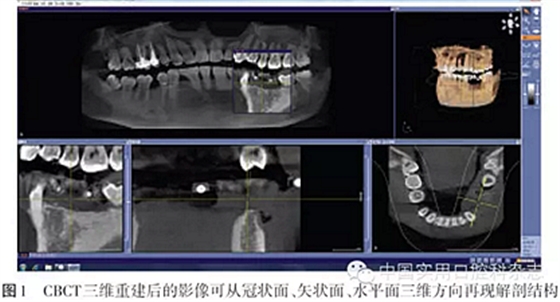

CT是20世紀70年代初放射診斷的一項重大突破。CT的多平面重組(multi-planar reformatting,MPR)和三維(3D)重組技術(shù)可將軸向、冠向和矢狀面斷層數(shù)據(jù)重組,進行多層橫截面斷層重建全景圖像,因而成為目前口腔種植最理想的放射線檢查技術(shù)[1]。最初的CT技術(shù)所需的放射線劑量很大,金屬會產(chǎn)生散射偽影,通常需要第三方軟件才能實現(xiàn)數(shù)據(jù)的導出和導入,儀器價格昂貴,必須要有經(jīng)過特殊培訓的專業(yè)人員才能操作。錐形束CT(cone beam computed tomography,CBCT)是20世紀90年代末發(fā)展起來的一種三維成像技術(shù),1998年首次報道了口腔頜面CBCT[2]。CBCT用三維錐形束X線掃描代替扇形束的螺旋CT掃描,獲得的直接數(shù)據(jù)是二維數(shù)據(jù),重建后得到三維圖像,因此金屬偽影小、重組數(shù)據(jù)的精確度高。CBCT的出現(xiàn)徹底改變了傳統(tǒng)口腔頜面放射學設(shè)備僅能提供二維圖像的歷史,可以三維顯示病變結(jié)構(gòu),大大提高了診斷能力(圖1)。CBCT已廣泛應(yīng)用于口腔種植術(shù)前診斷與設(shè)計、牙體牙髓病、牙周疾病、顳下頜關(guān)節(jié)疾病、口腔頜面部骨折和腫瘤等領(lǐng)域,在三維測量、診斷分析方面已經(jīng)取代了傳統(tǒng)的放射線檢查技術(shù)。